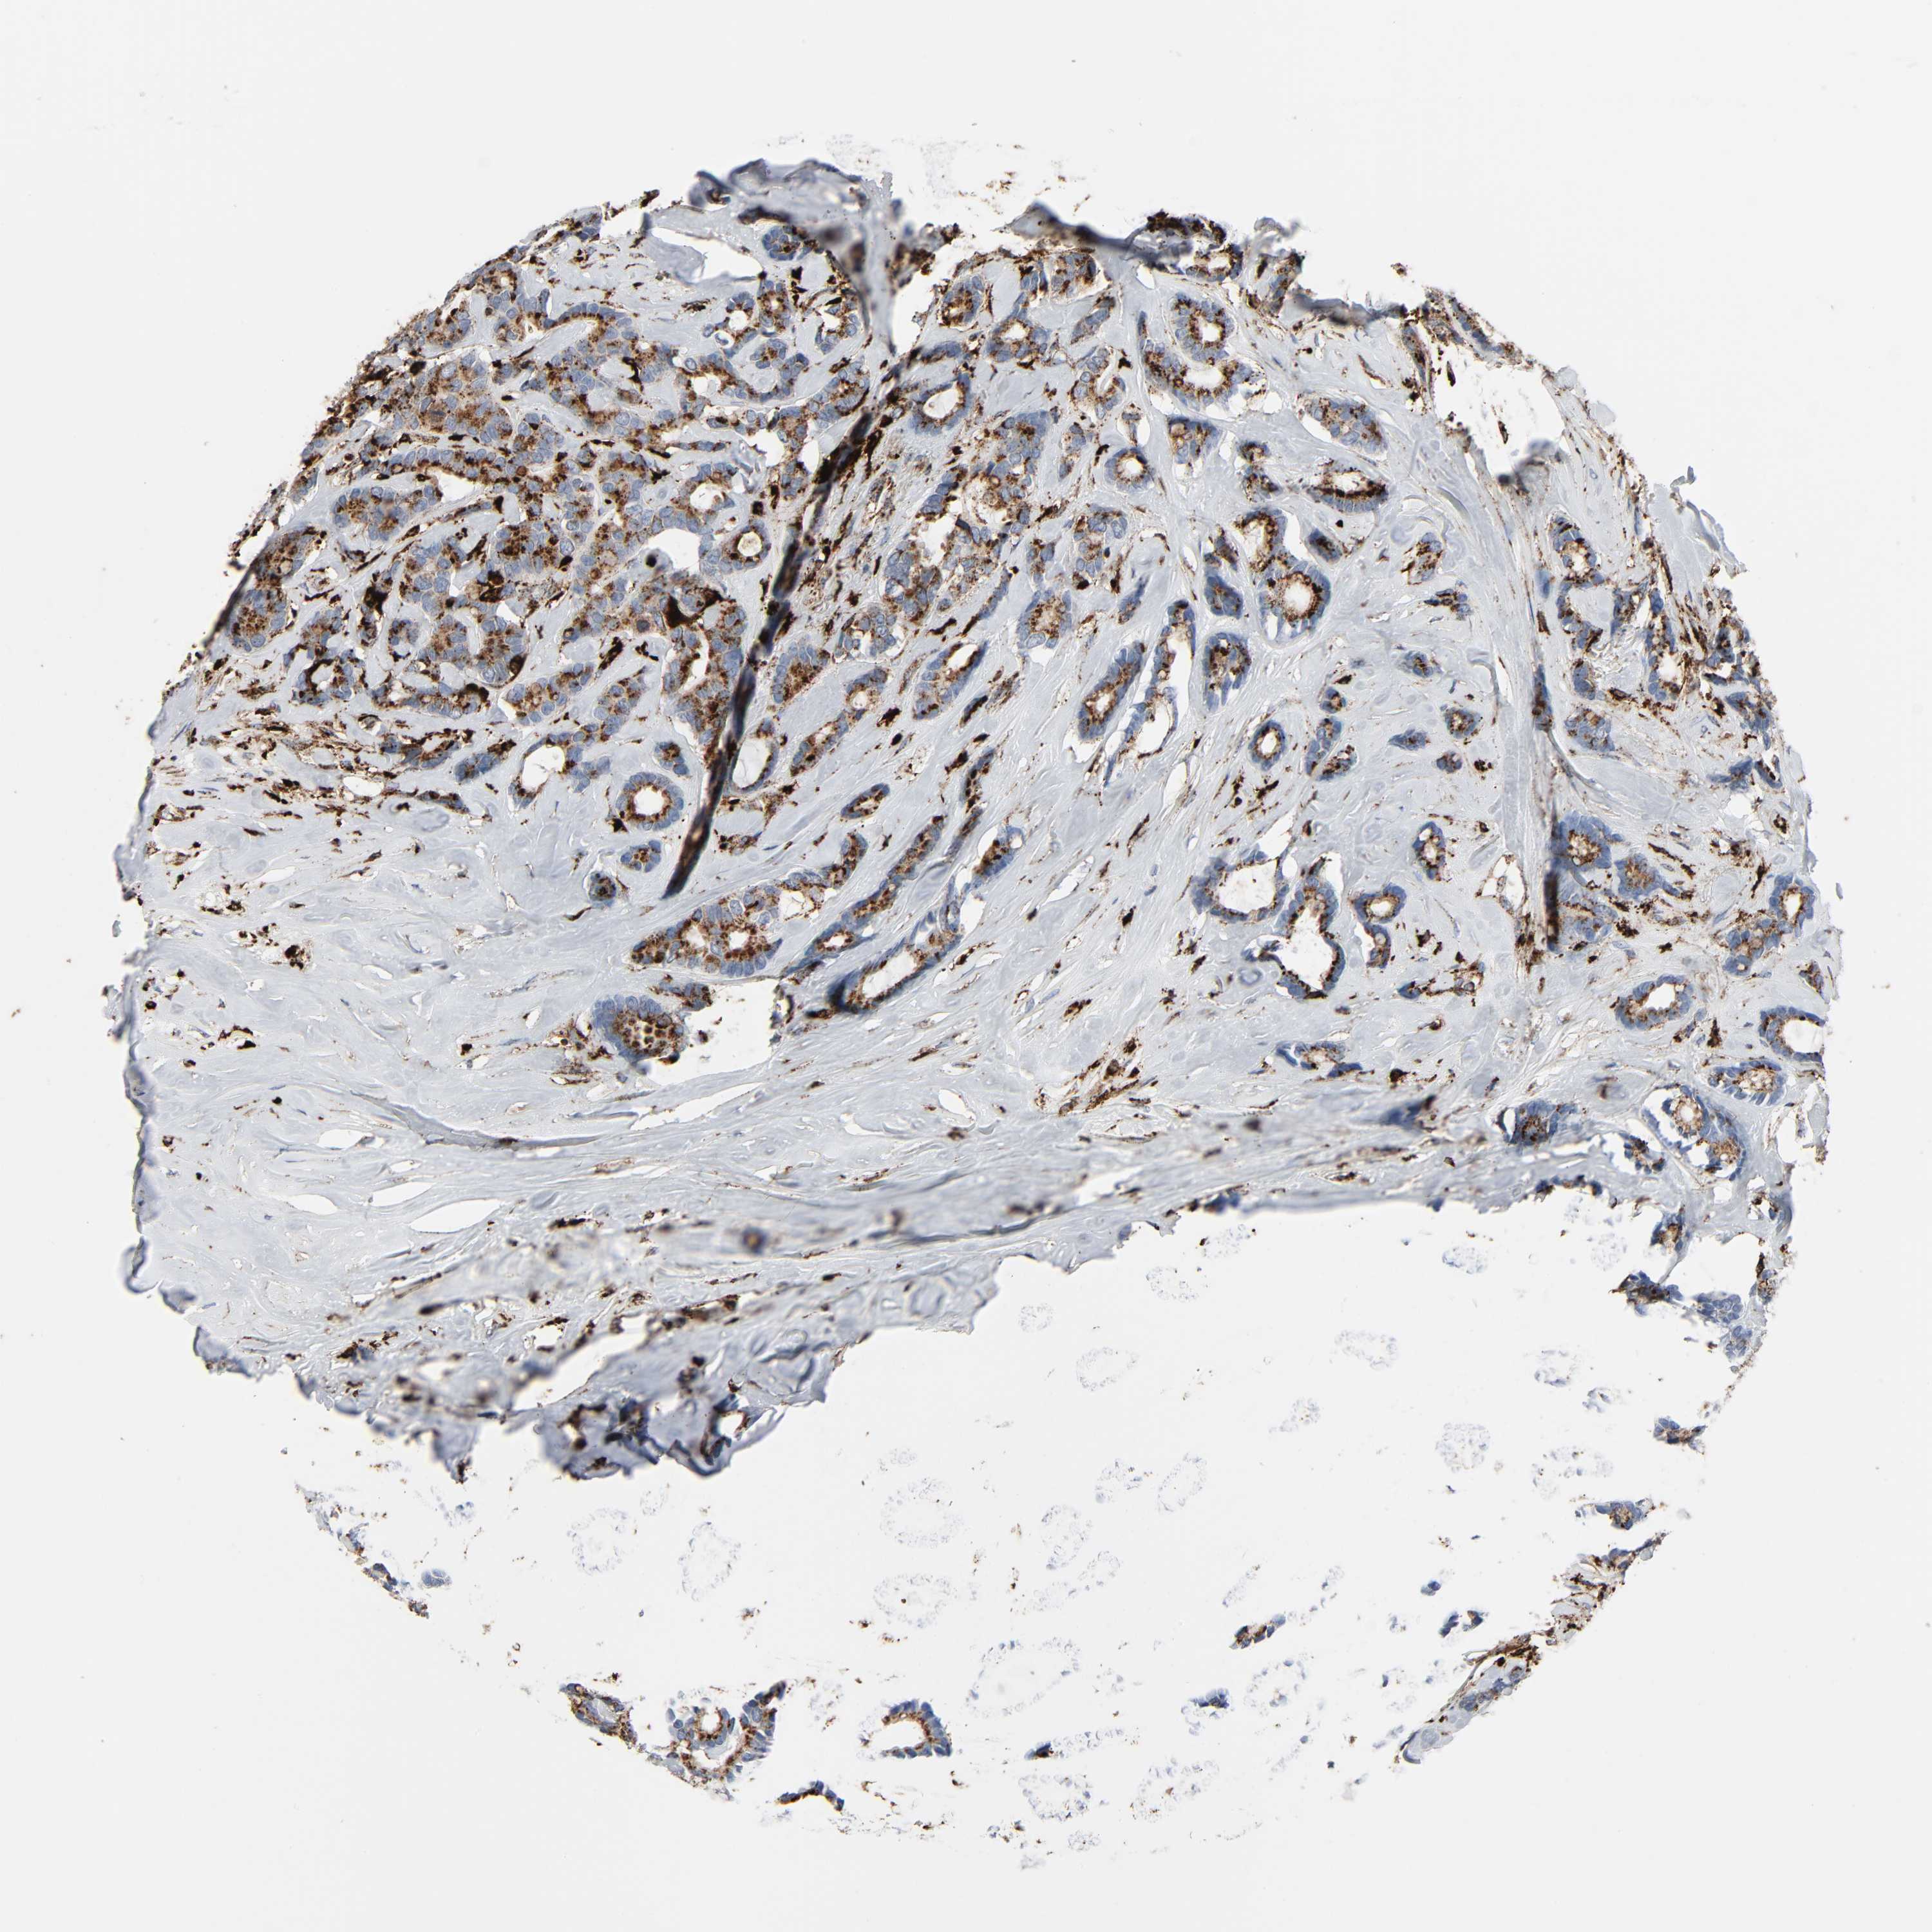

CANCER BREAST CANCER Show tissue menu

BRCA TCGA BRCA VALIDATION PROTEIN EXPRESSION